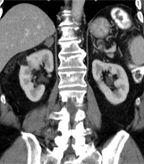

Renal angiomyolipoma: right kidney lesion in CT; source: Hellerhoff, Wikimedia Commons